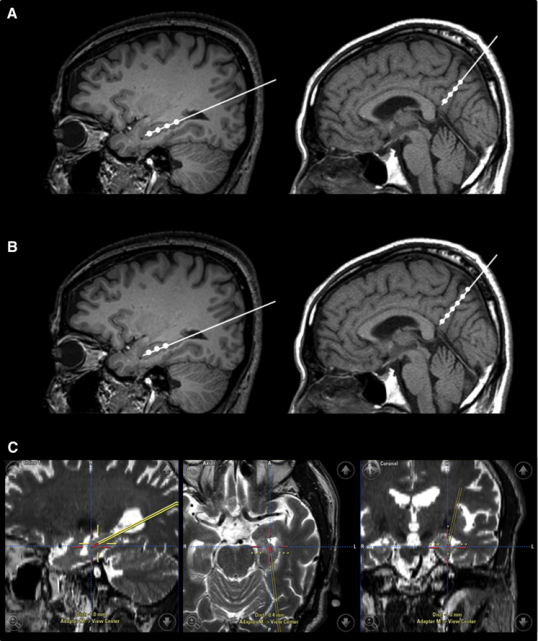

2015年,韓國首爾三星醫療中心招募了9名輕度至中度癡呆的阿爾茨海默氏病患者。Kim對9名患者進行了一項立體定向注射間充質干細胞的I期臨床試驗。

三名患者接受低劑量(1.0×107細胞/2 mL),6名患者接受高劑量(3.0×107hUCB-MSC 的細胞/2 mL) 。9名患者進行了三次干細胞注射(每隔4周一次)。

在之后長達36個月的跟蹤研究期間, 沒有患者出現嚴重的不良事件。由此可見, 干細胞治療阿爾茲海默癥是可行、安全且耐受性良好的。